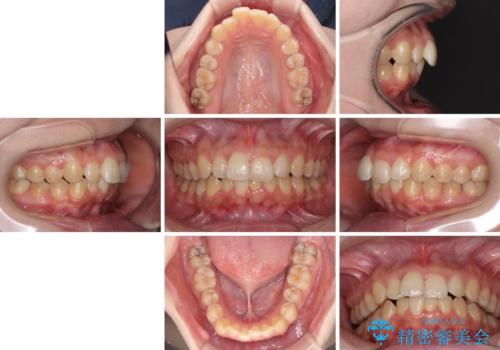

前歯のデコボコをインビザライン矯正で綺麗に改善

- 上下前歯のデコボコを気にして来院された患者様です。

全体的に叢生は軽度であったため、インビザラインにて矯正治療を行うこととしました。

舌の突出癖改善がうまくいかず、途中で舌小帯の切除を行いました。

気になる段差を納得いくまで改善させたため、治療期間は長くなりましたが、綺麗な仕上がりとなりました。